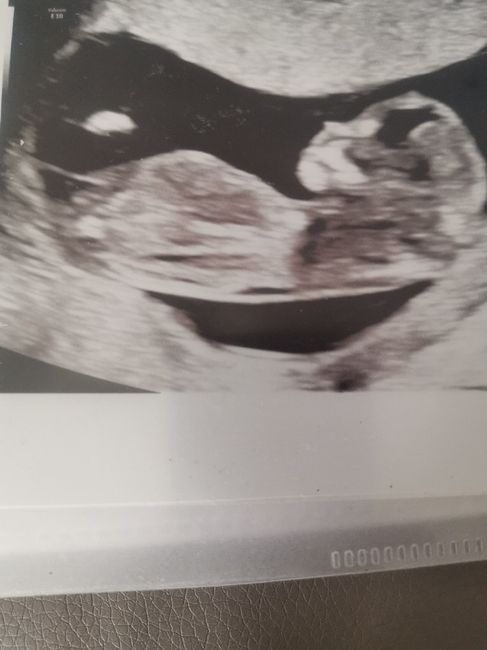

Ho anche quella fatta alla translucenza nucale la settimana prima che vi lascio qui sotto dove però mi hanno detto che era presto per sapere.